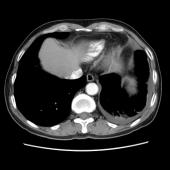

[影像描述]

左肺下叶可见高密度肿块影,边界清晰,边缘不规则,左肺下叶支气管局部截断,增强后病灶边缘轻度强化,中心未见明显强化;左侧胸腔内可见液性密度影;纵隔内未见明确肿大淋巴结影。

(左下叶)肺肉瘤样癌(巨细胞癌),伴大片坏死

肺肉瘤样癌是一种少见的非小细胞肺癌,WHO将其分为5个亚型:多形性癌、梭形细胞癌、具巨细胞癌、癌肉瘤和肺肉瘤。主要见于老年患者,男多于女,临床症状与肿瘤生长部位及侵犯周围组织的情况有关,中央型较易侵犯支气管,症状往往出现较早。CT多表现为肺内单发肿块影,最大径一般大于5cm,周围型多于中央型,可跨叶生长;边缘光滑或清晰;毛刺征及胸膜牵拉症少见;坏死、空腔及分叶、支气管截断多见,坏死边界不清,可见坏死内强化灶,肺门及纵隔淋巴结转移多为环形强化。需要鉴别以下几种疾病:肺结核球呈圆形或类圆形,多数密度不均匀,周边或中央常可见钙化,病灶中心有时可见小空洞。病灶边缘清楚,部分边缘可呈浅分叶状,少数可见毛刺征或胸膜凹陷征,周围常可见卫星灶。增强检查病灶不强化或仅轻度强化。周围型错构瘤直径多在2.5cm以下,瘤体内可见斑点状或爆米花状钙化,部分病变有脂肪密度,多数病变边缘清楚、光滑,CT增强大多数病灶无明显强化。肺炎性假瘤呈圆形或类圆形高密度影,密度较均匀,边缘多清楚而光滑,少数可呈毛刺样改变,增强检查大多数肿块较显著均匀强化。